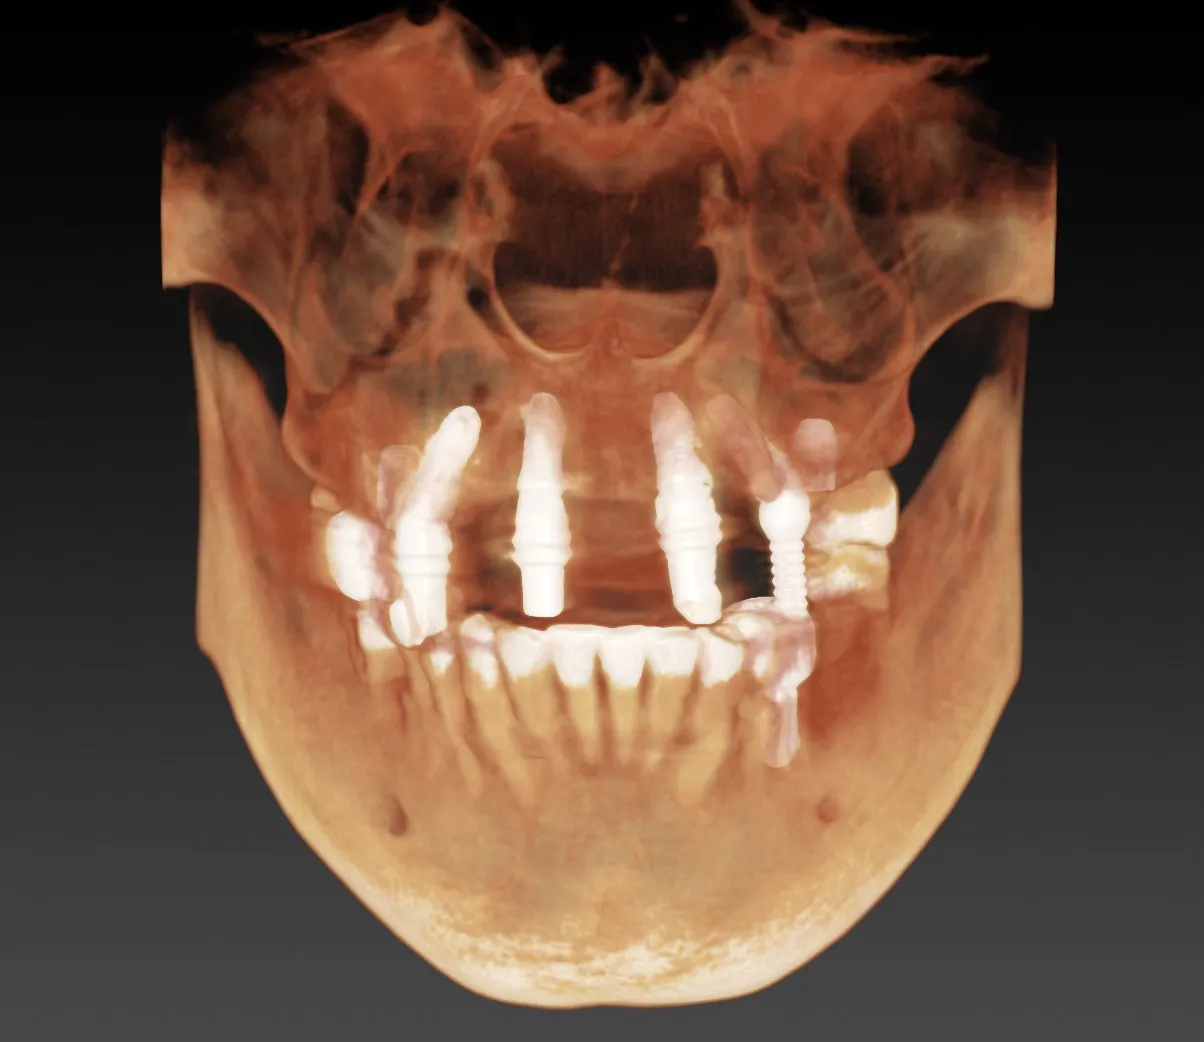

All treatments begin with a CBCT scan and digital planning using 3Shape and Exocad software to ensure optimal placement, esthetics, and long-term performance.

Most patients are surprised at how comfortable the process is. Dr. Khuu is known for his gentle touch, with many patients falling asleep during their procedure. With advanced technology like CBCT-guided surgical planning and minimally invasive techniques using ultrasonic bone surgery units, implant placement is precise, efficient, and designed to minimize discomfort.

When planned and placed correctly, implants typically last for life. Dr. Khuu focuses on long-term success, not just quick fixes. By combining CBCT scans, intraoral scans, and Exocad digital workflows, he ensures every implant integrates properly, functions naturally, and provides predictable, long-lasting results.

Most adults missing one or more teeth are candidates, but the key is proper evaluation. Dr. Khuu uses 3D imaging and advanced digital planning to assess bone density, gum health, and bite alignment. If bone support is limited, he offers bone grafting and other advanced procedures to prepare the foundation, ensuring implants succeed in even complex cases.